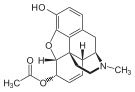

Several semi-synthetic opioids were developed in Germany in the 1910s. The first, oxymorphone, was synthesized from thebaine, an opioid alkaloid in opium poppies, in 1914.[228] Next, Martin Freund and Edmund Speyer developed oxycodone, also from thebaine, at the University of Frankfurt in 1916.[229] In 1920, hydrocodone was prepared by Carl Mannich and Helene Löwenheim, deriving it from codeine. In 1924, hydromorphone was synthesized by adding hydrogen to morphine. Etorphine was synthesized in 1960, from the oripavine in opium poppy straw. Buprenorphine was discovered in 1972.[228]